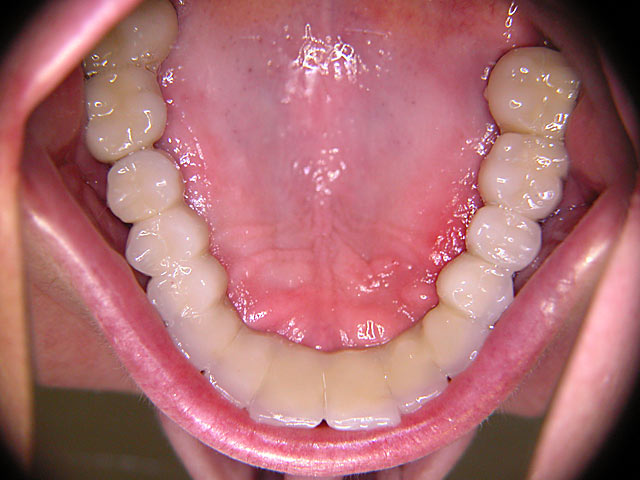

Die folgenden Patientenfälle sollen Ihnen einen Einblick in die Möglichkeiten der modernen Implantation geben.

Implantation – Patientenbeispiel 1: